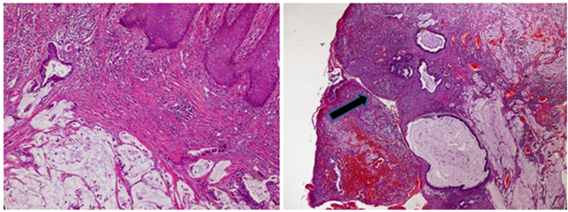

We report a case of a 44-year-old patient with a 20-year medical history of CD. He underwent ileocecal resection at age of 22 years. He had poor treatment adherence and a lapse in clinical follow-ups in recent years. He was referred to our hospital for recurrent and refractory perineal complex fistula. The examination of the perineum showed 4 productive external fistulas with purulent secretion and an ulceration of 4 cm (Figure 1). The digital rectal examination revealed no mass. Colonoscopy showed signs of left-sided congestive and ulcerative colitis, along with inflammatory pseudo-polyps. On pelvic MRI, a complex trans-sphincteric fistula with four primary orifices was observed, along with a 4 cm perianal abscess extending into both ischioanal fossae (Figure 2). Examination under anaesthesia was performed, abcess was drained and multiple biopsies were taken. The histopathological analysis concluded to a mucinous adenocarcinoma originating from the anal fistula (Figure 3). Thoraco-abdomino pelvic CT scan showed no metastases. Abdominoperineal resection was indicated but the patient refused surgery.

Figure 3 Histological Examination: infiltration of the anal mucosa by adenocarcinoma, the fistula is infiltrated by the adenocarcinoma (arrow).